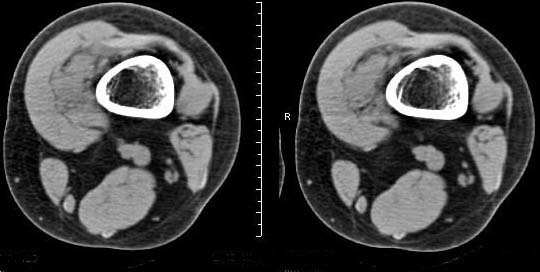

女,24岁,左大腿下部近膝关节处偏内侧有一软组织包块,触之有压痛,平扫示病灶密度不均,形态及轮廓欠规则,无包膜,与周围组织界限不清,增强后显示有明显强化且不均匀强化,本人考虑为该软组织肿块为恶性病变。请大家发表高见!